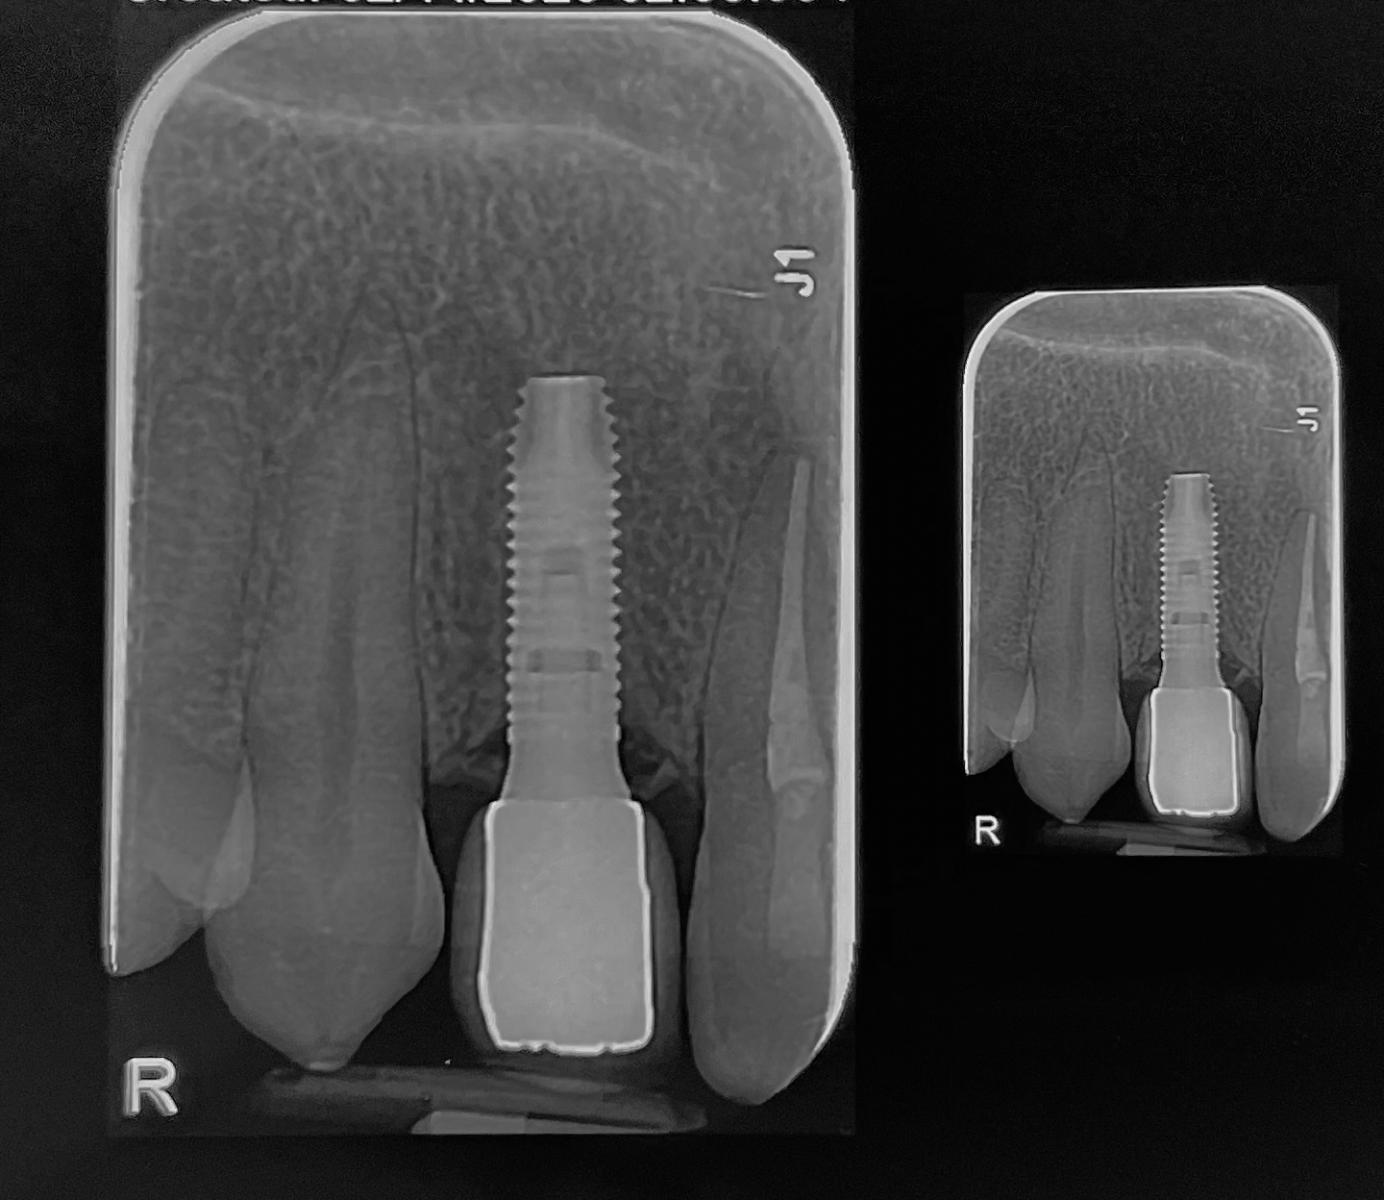

جایگزینی دندان ثنایای کناری فک بالا با ایمپلنت

جایگزینی دندان ثنایای کناری فک بالا با ایمپلنت SIC سوییس و روکش نهایی آن,فرم گرفتن طبیعی لثه در اطراف ایمپلنت و روکش.